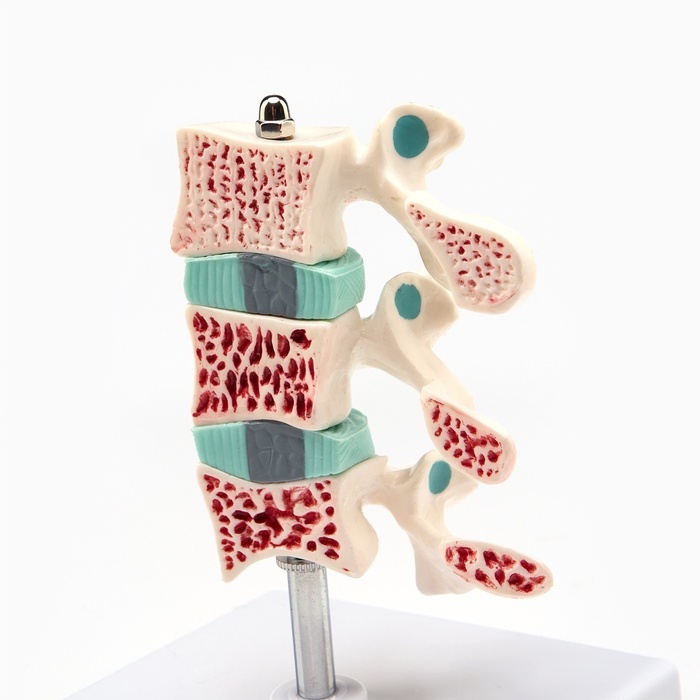

ЕКБ 167

No Brand, артикул: 7072352